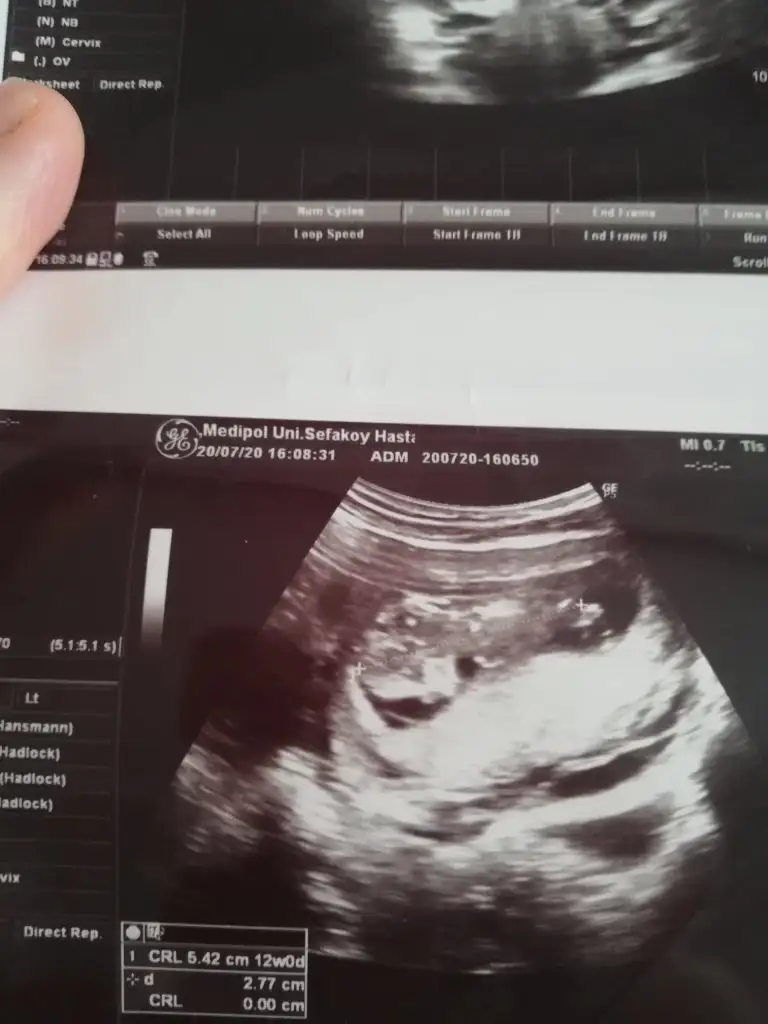

Erkek gibi 12-13 hafta olursa tekrar usg paylaşınBenimkini de tahminde bulunabilecek var mı 11. Hafta :))

TeşekkürlerErkek gibi 12-13 hafta olursa tekrar usg paylaşın